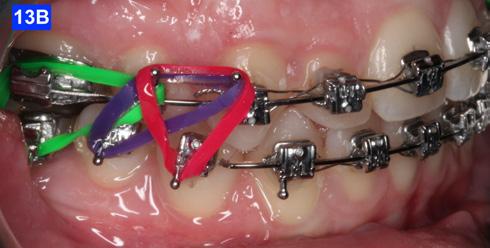

Class III inter-arch elastics (1/4” – 4.5 oz) were introduced to improve the inter-digitation (Figure 12 – A, B).

Three months before de-bracketing, while the patient had a .019 x .025 SS arch wire in the maxilla and the mandible, we appointed her for “Count down on retention.” The full arch wire was left in the maxilla, however, in the mandible, it was cut and bent-in, just distally to cuspids. Two triangular elastics were placed per sextant (1/4”– 4.5 oz.) for refinement of the tooth-to-tooth inter-digitation (Figure 13 - A, B, C).8

Figure 13A: Pre-de-bracketing, frontal view

Figure 13B: Pre-de-bracketing, right lateral view

Figure 13C: Pre-de-bracketing, left lateral view